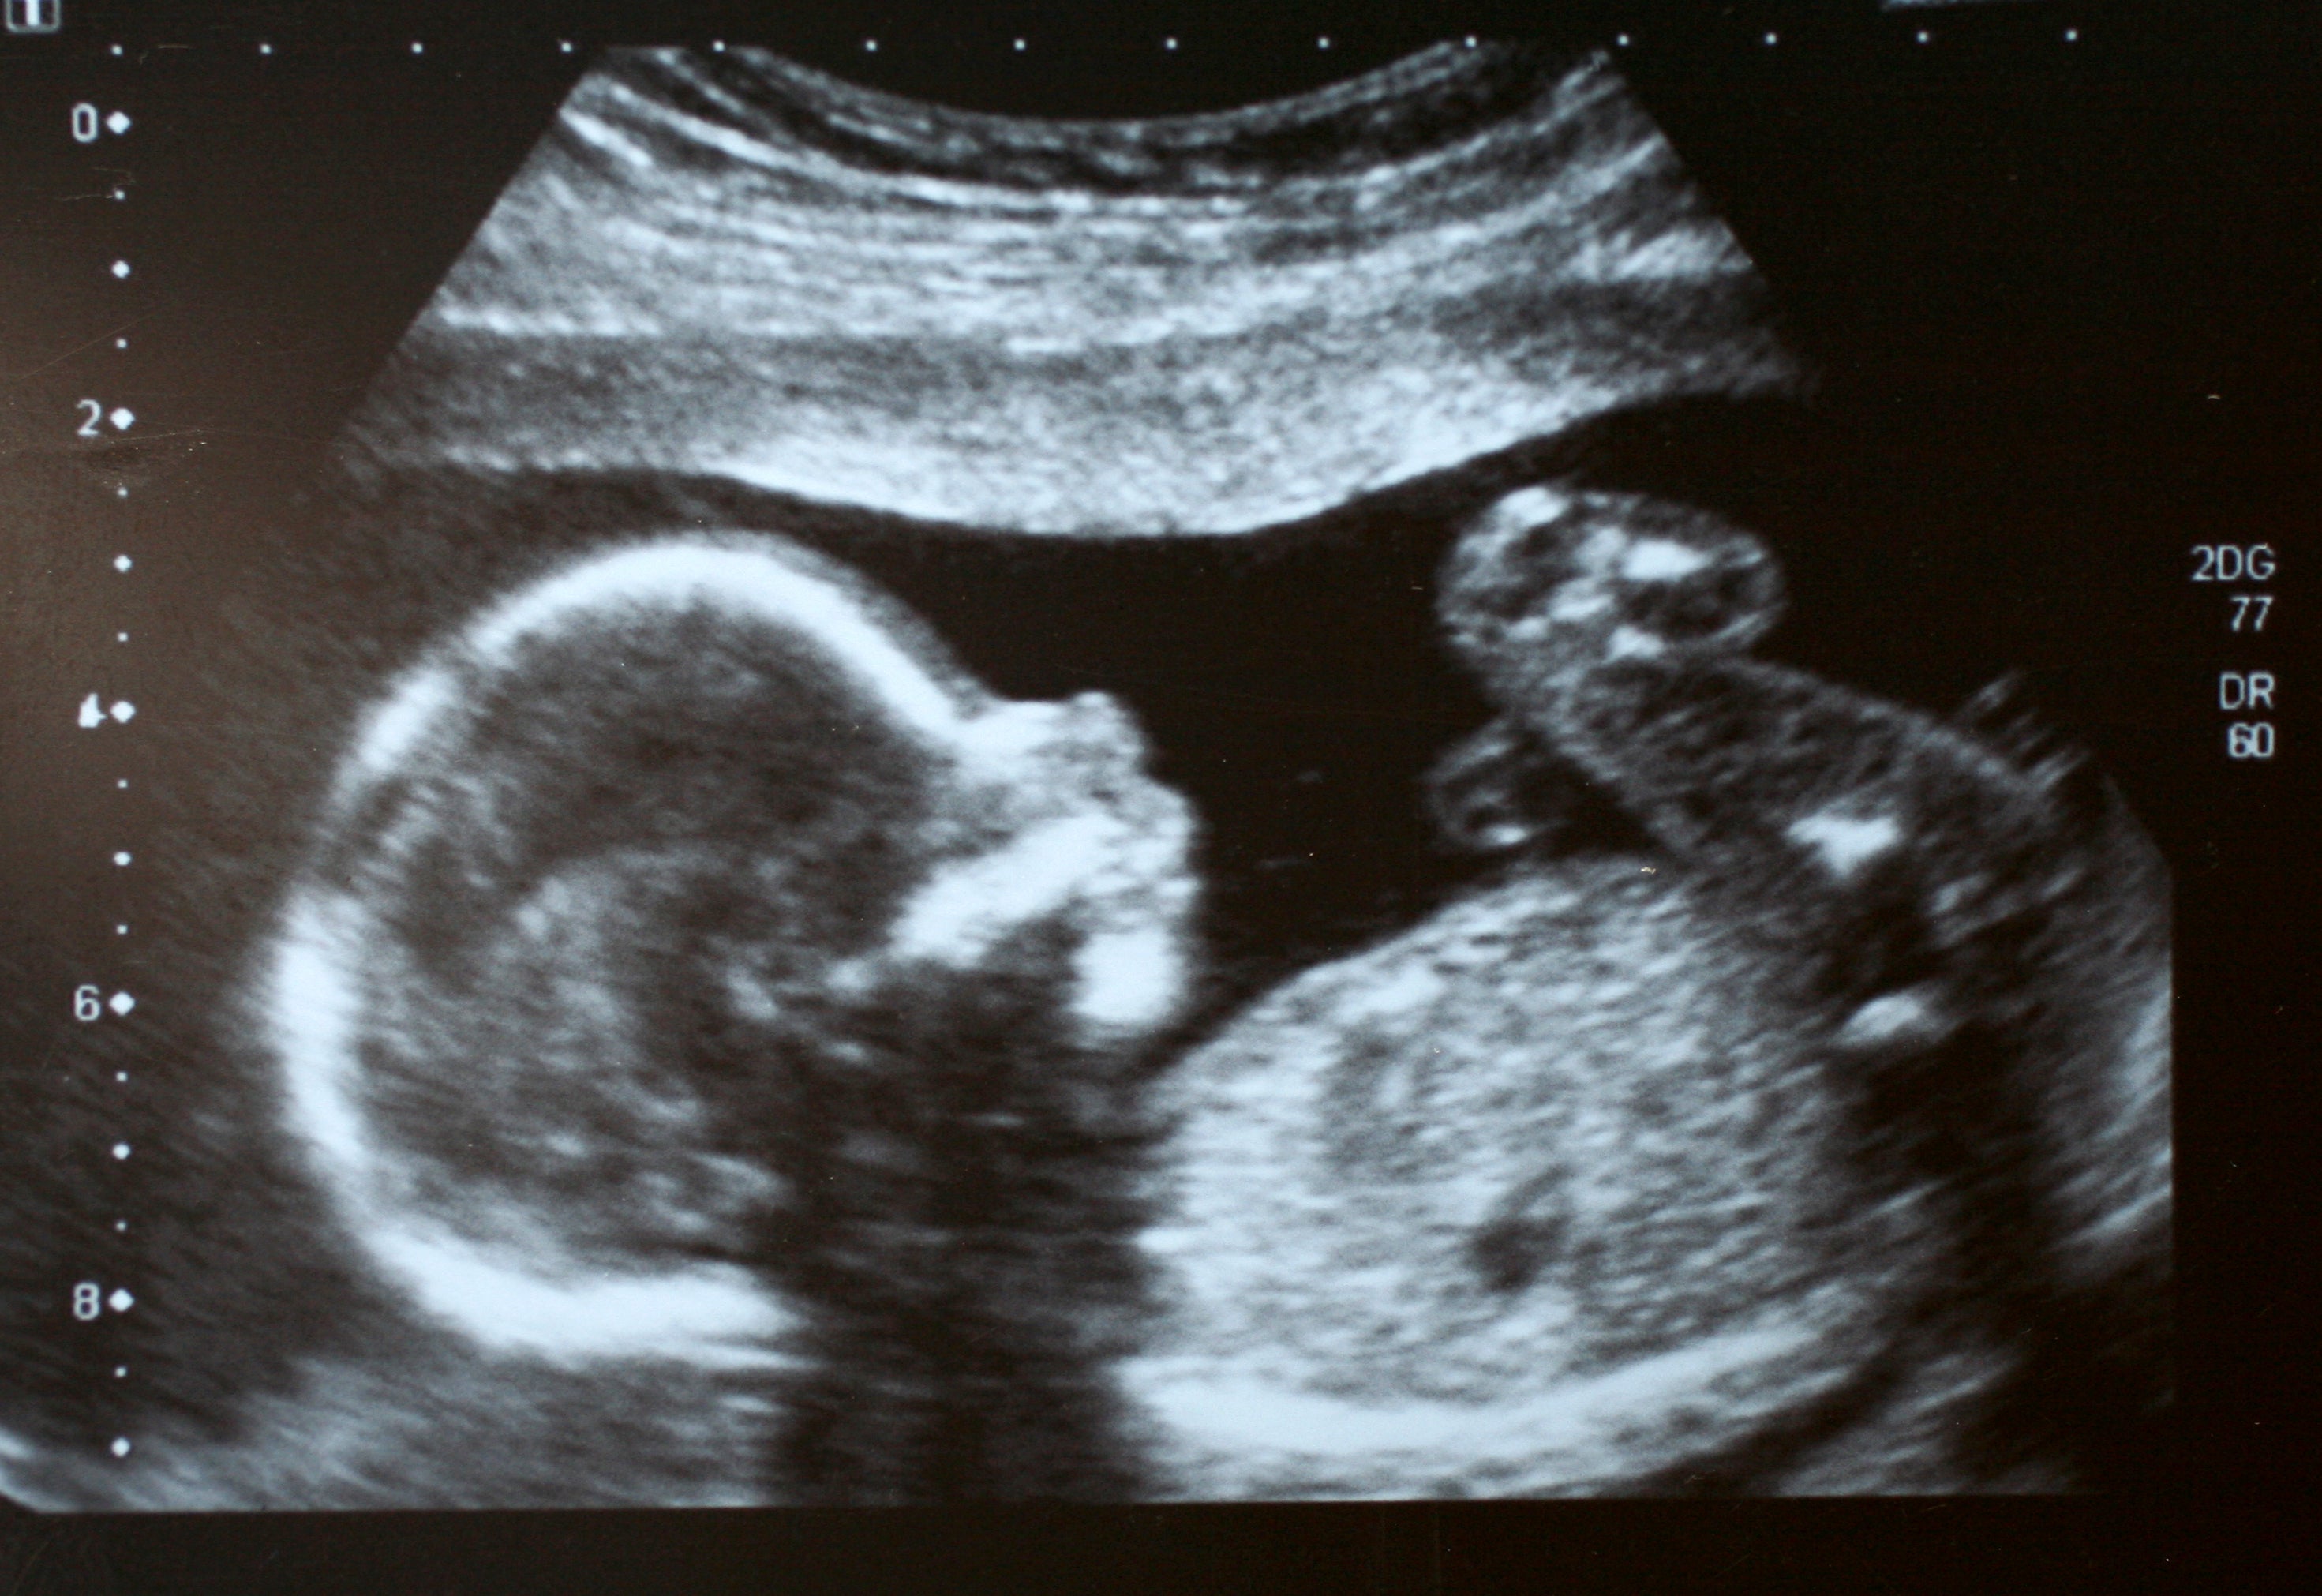

Thompson explains that if something unexpected shows up, it might not be picked up, or could be incorrectly diagnosed. “Or sometimes it’s seen,” she adds, “but nothing is done about it. “You expect that if someone’s got a uniform on, they’ll have the right qualifications. And most of the time, nothing is wrong. But when something is wrong, that’s when it can have a devastating impact.”

Some women have even been told - incorrectly - that their baby has died. Inevitably, even if a later scan confirms this to be false, the ensuing anxiety stemming from incompetency like this is excruciating and cruel.

But not all clinics are following that guidance, or using properly maintained equipment, despite booking back-to-back scans all day, generating huge profit margins. Even in the last few weeks, Katie has seen these issues in action: recently it was a woman who had been told by a private clinic that she had miscarried.

“She’d been told her pregnancy sac was empty,” Katie says. “But when I scanned her, there was actually a large bleed next to a perfectly normal early pregnancy. The private clinic had misdiagnosed the bleed as the sac. She’d spent days thinking she’d lost her baby.”